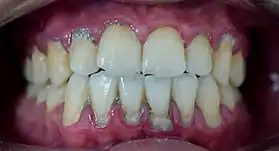

Plaque accumulation causes the gingiva to become irritated and inflamed, and this is referred to as gingivitis. When the gingiva become so irritated that there is a loss of the connective tissue fibers that attach the gums to the teeth and bone that surrounds the tooth, this is known as periodontitis. Dental plaque is not the sole cause of periodontitis; however it is many times referred to as a primary aetiology. Plaque that remains in the oral cavity long enough will eventually calcify and become calculus.[15] Calculus is detrimental to gingival health because it serves as a trap for increased plaque formation and retention; thus, calculus, along with other factors that cause a localized build-up of plaque, is referred to as a secondary aetiology of periodontitis.

When plaque is supragingival, the bacterial content contains a great proportion of aerobic bacteria and yeast,[18] or those bacteria which utilize and can survive in an environment containing oxygen. Subgingival plaque contains a higher proportion of anaerobic bacteria, or those bacteria which cannot exist in an environment containing oxygen. Several anaerobic plaque bacteria, such as Porphyromonas gingivalis,[19] secrete antigenic proteins that trigger a strong inflammatory response in the periodontium, the specialized tissues that surround and support the teeth. Prolonged inflammation of the periodontium leads to bone loss and weakening of the gingival fibers that attach the teeth to the gums, two major hallmarks of periodontitis. Supragingival calculus formation is nearly ubiquitous in humans,[20][21][22] but to differing degrees. Almost all individuals with periodontitis exhibit considerable subgingival calculus deposits.[15] Dental plaque bacteria have been linked to cardiovascular disease[23] and mothers giving birth to pre-term low weight infants,[24] but there is no conclusive evidence yet that periodontitis is a significant risk factor for either of these two conditions.[25]